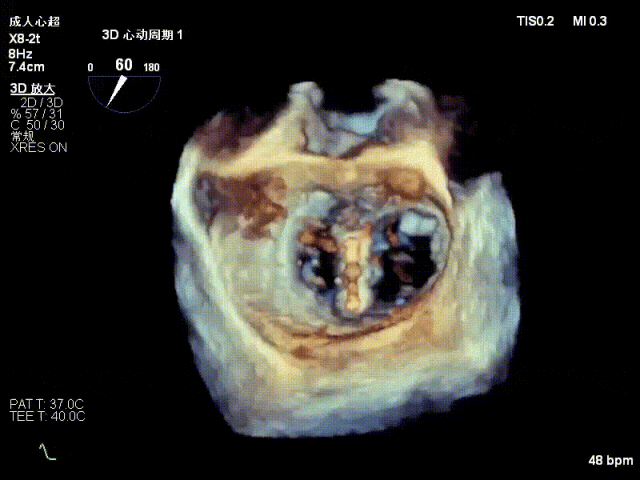

术中超声要点

术前术后对比图

术前

术后

术后,出院检查报告显示夹子位置固定,二尖瓣、三尖瓣及主动脉轻微反流,左房增大,左室内径正常上限,EF值正常下限(WMSI 1分)。